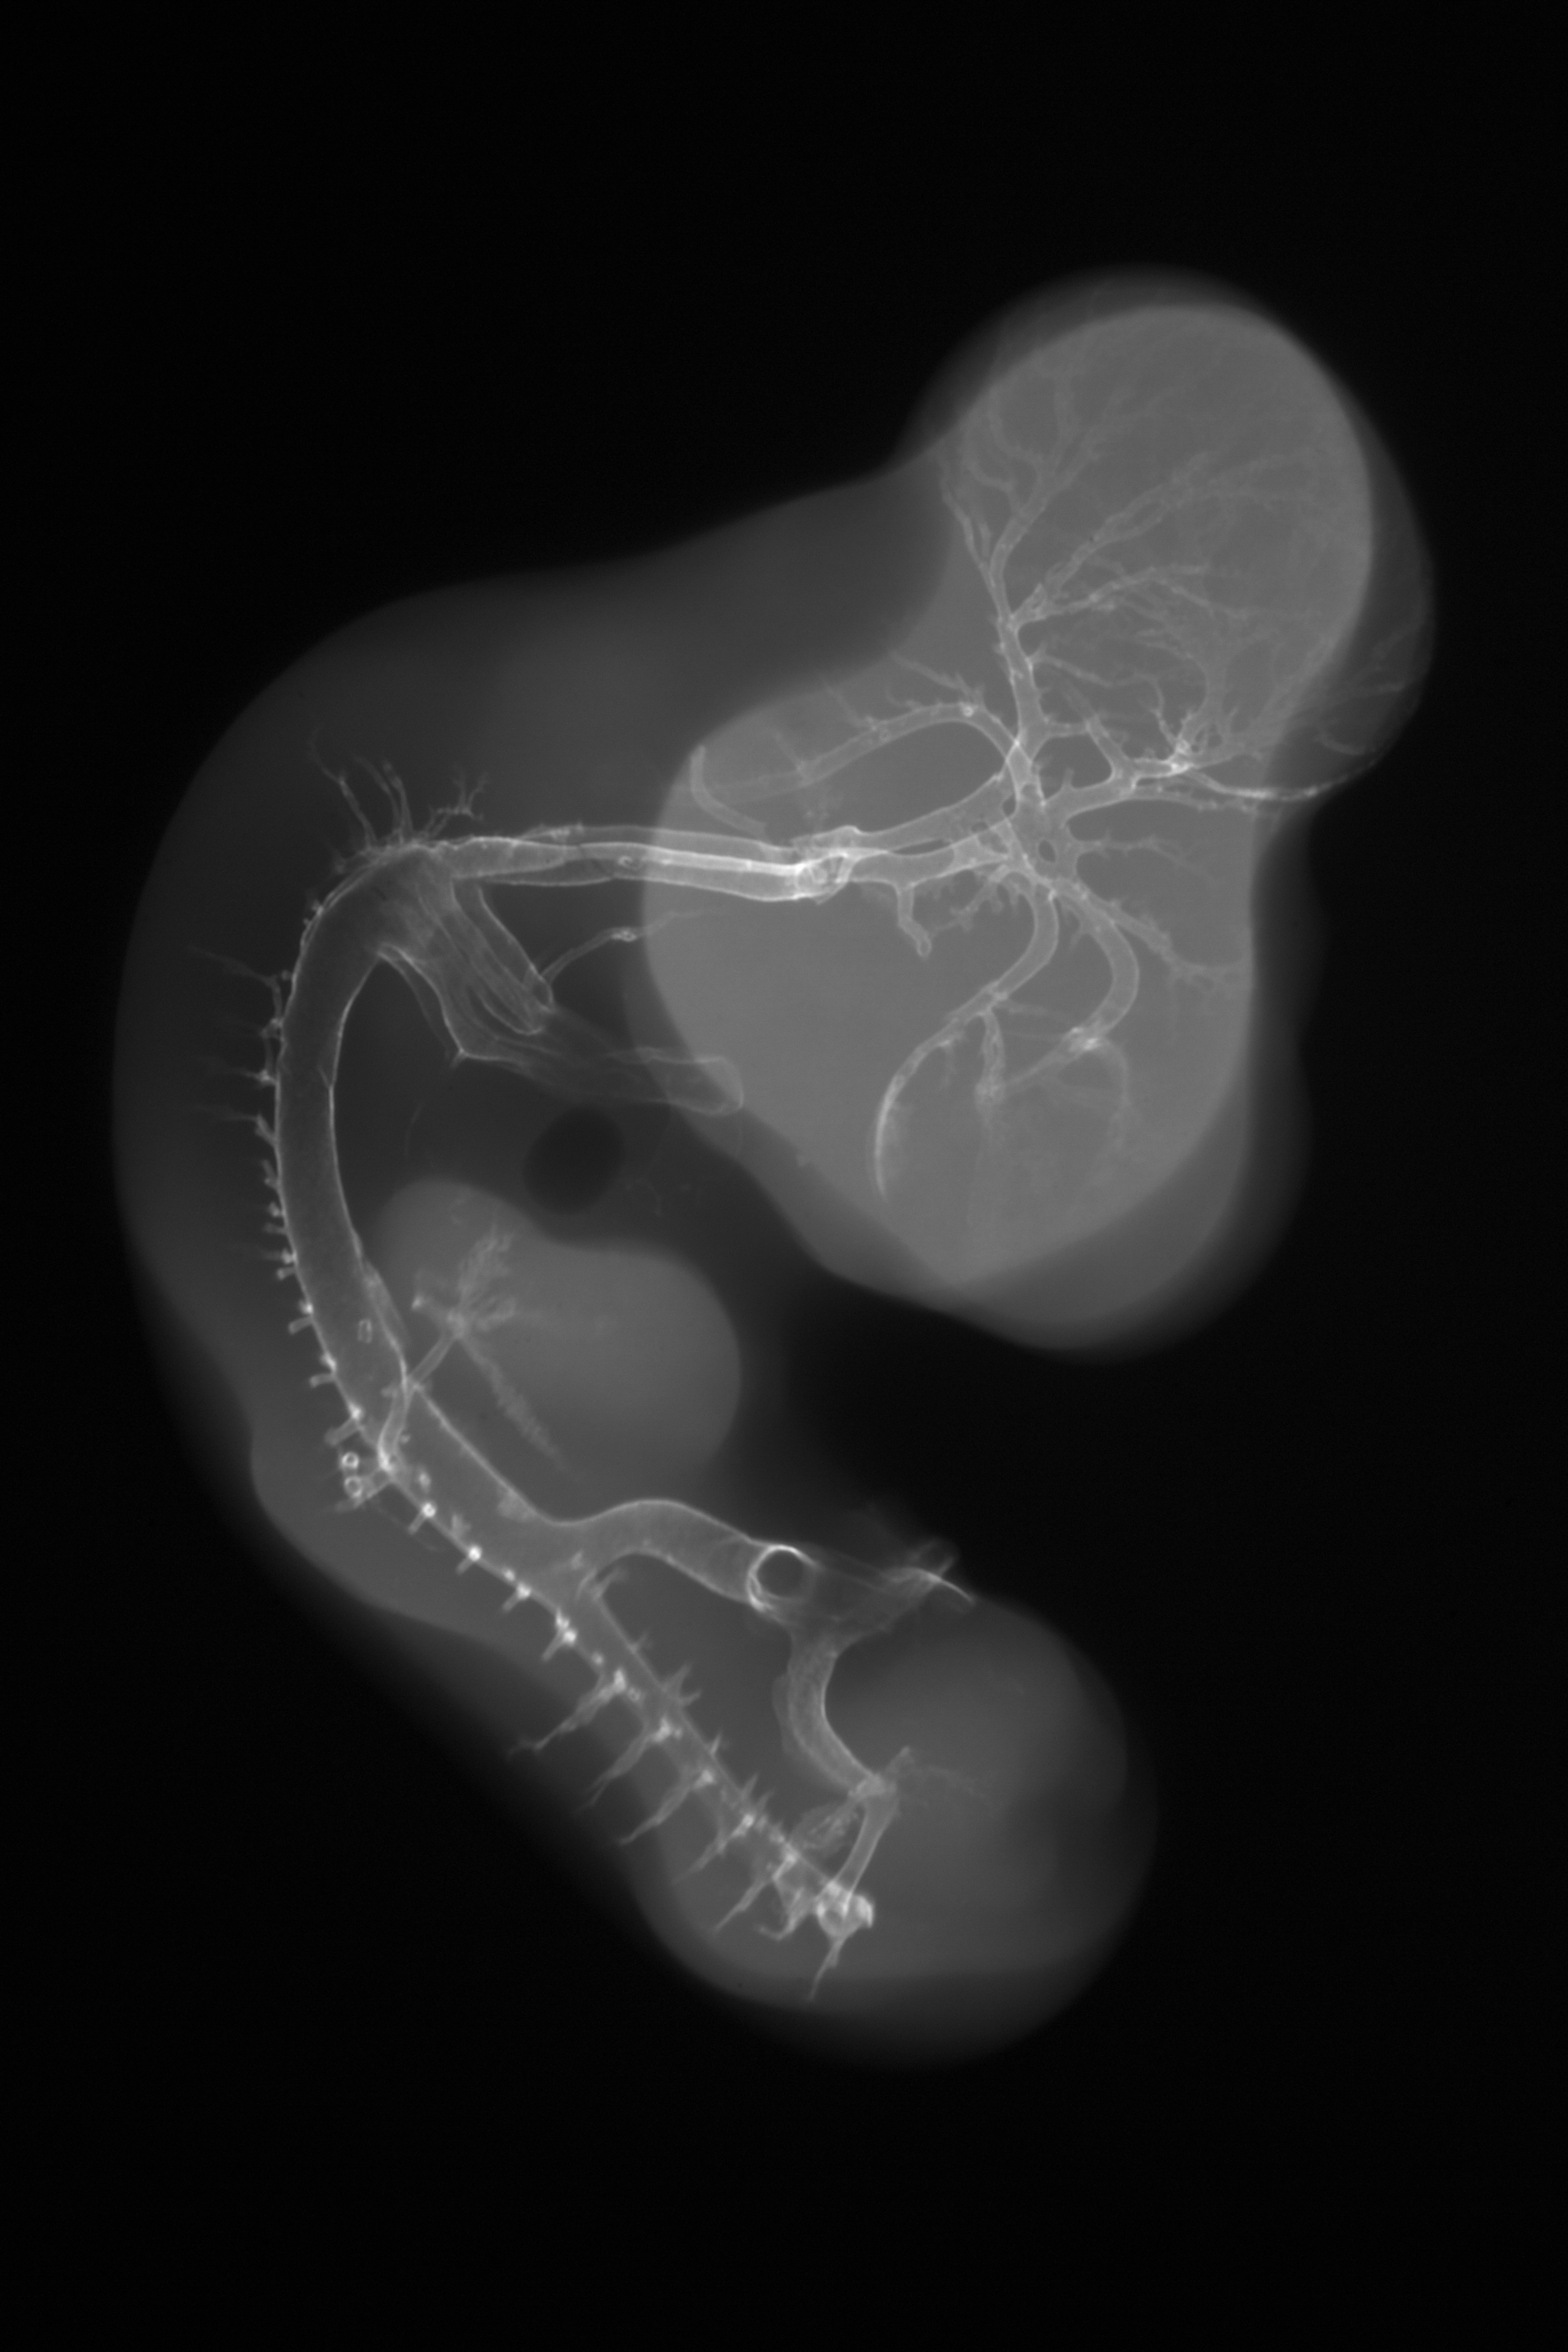

Hamburger-Hamilton (HH) Stage 26 (approx. 5 days)

X-Ray Micrographs